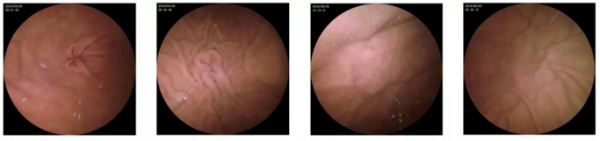

专利三镜片镜头,最小可视精度0.04mm 胶囊内置专利三镜片镜头,图像视野大,景深0-50mm,图像分辨力高,畸变控制低于5%,图像不失真不变形,胃部细节捕捉更精准。

医生可实时查看胃部高清影像,并标记关键部位及疑似病灶部位,10-15分钟实现对胃内六大部位的全方位检查。强大的智能阅片功能,可自动对海量图像智能筛选,识别过滤高重复图片,高效提升医生检查效率。